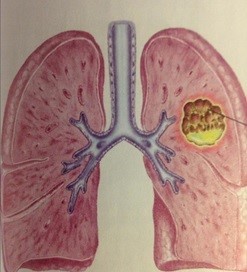

Áp xe phổi Hướng dẫn phòng tránh và xử lý kịp thời

áp xe phổi

- Áp xe phổi Giải mã những thông tin quan trọng cần biết

- Áp xe phổi Giải mã nguyên nhân, triệu chứng và hướng xử trí